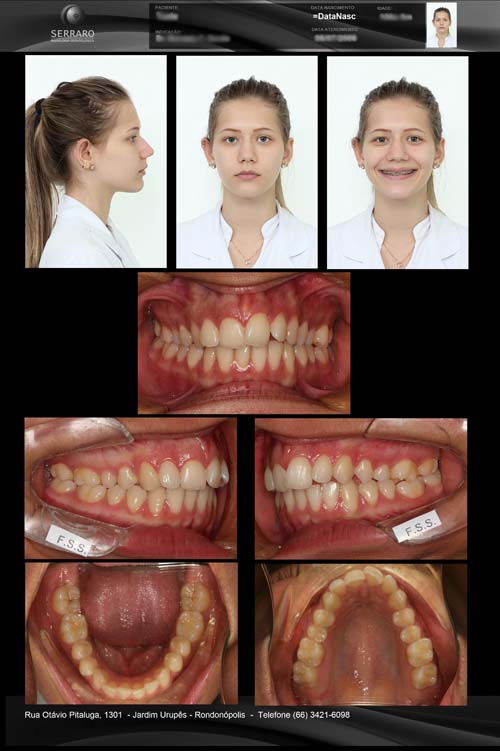

• PAINEL DE FOTOS

DOCUMENTAÇÃO STANDER

ESTETICA

• PAINEL DE FOTOS DOCUMENTAÇÃO ORTODONTICA COMPLETA